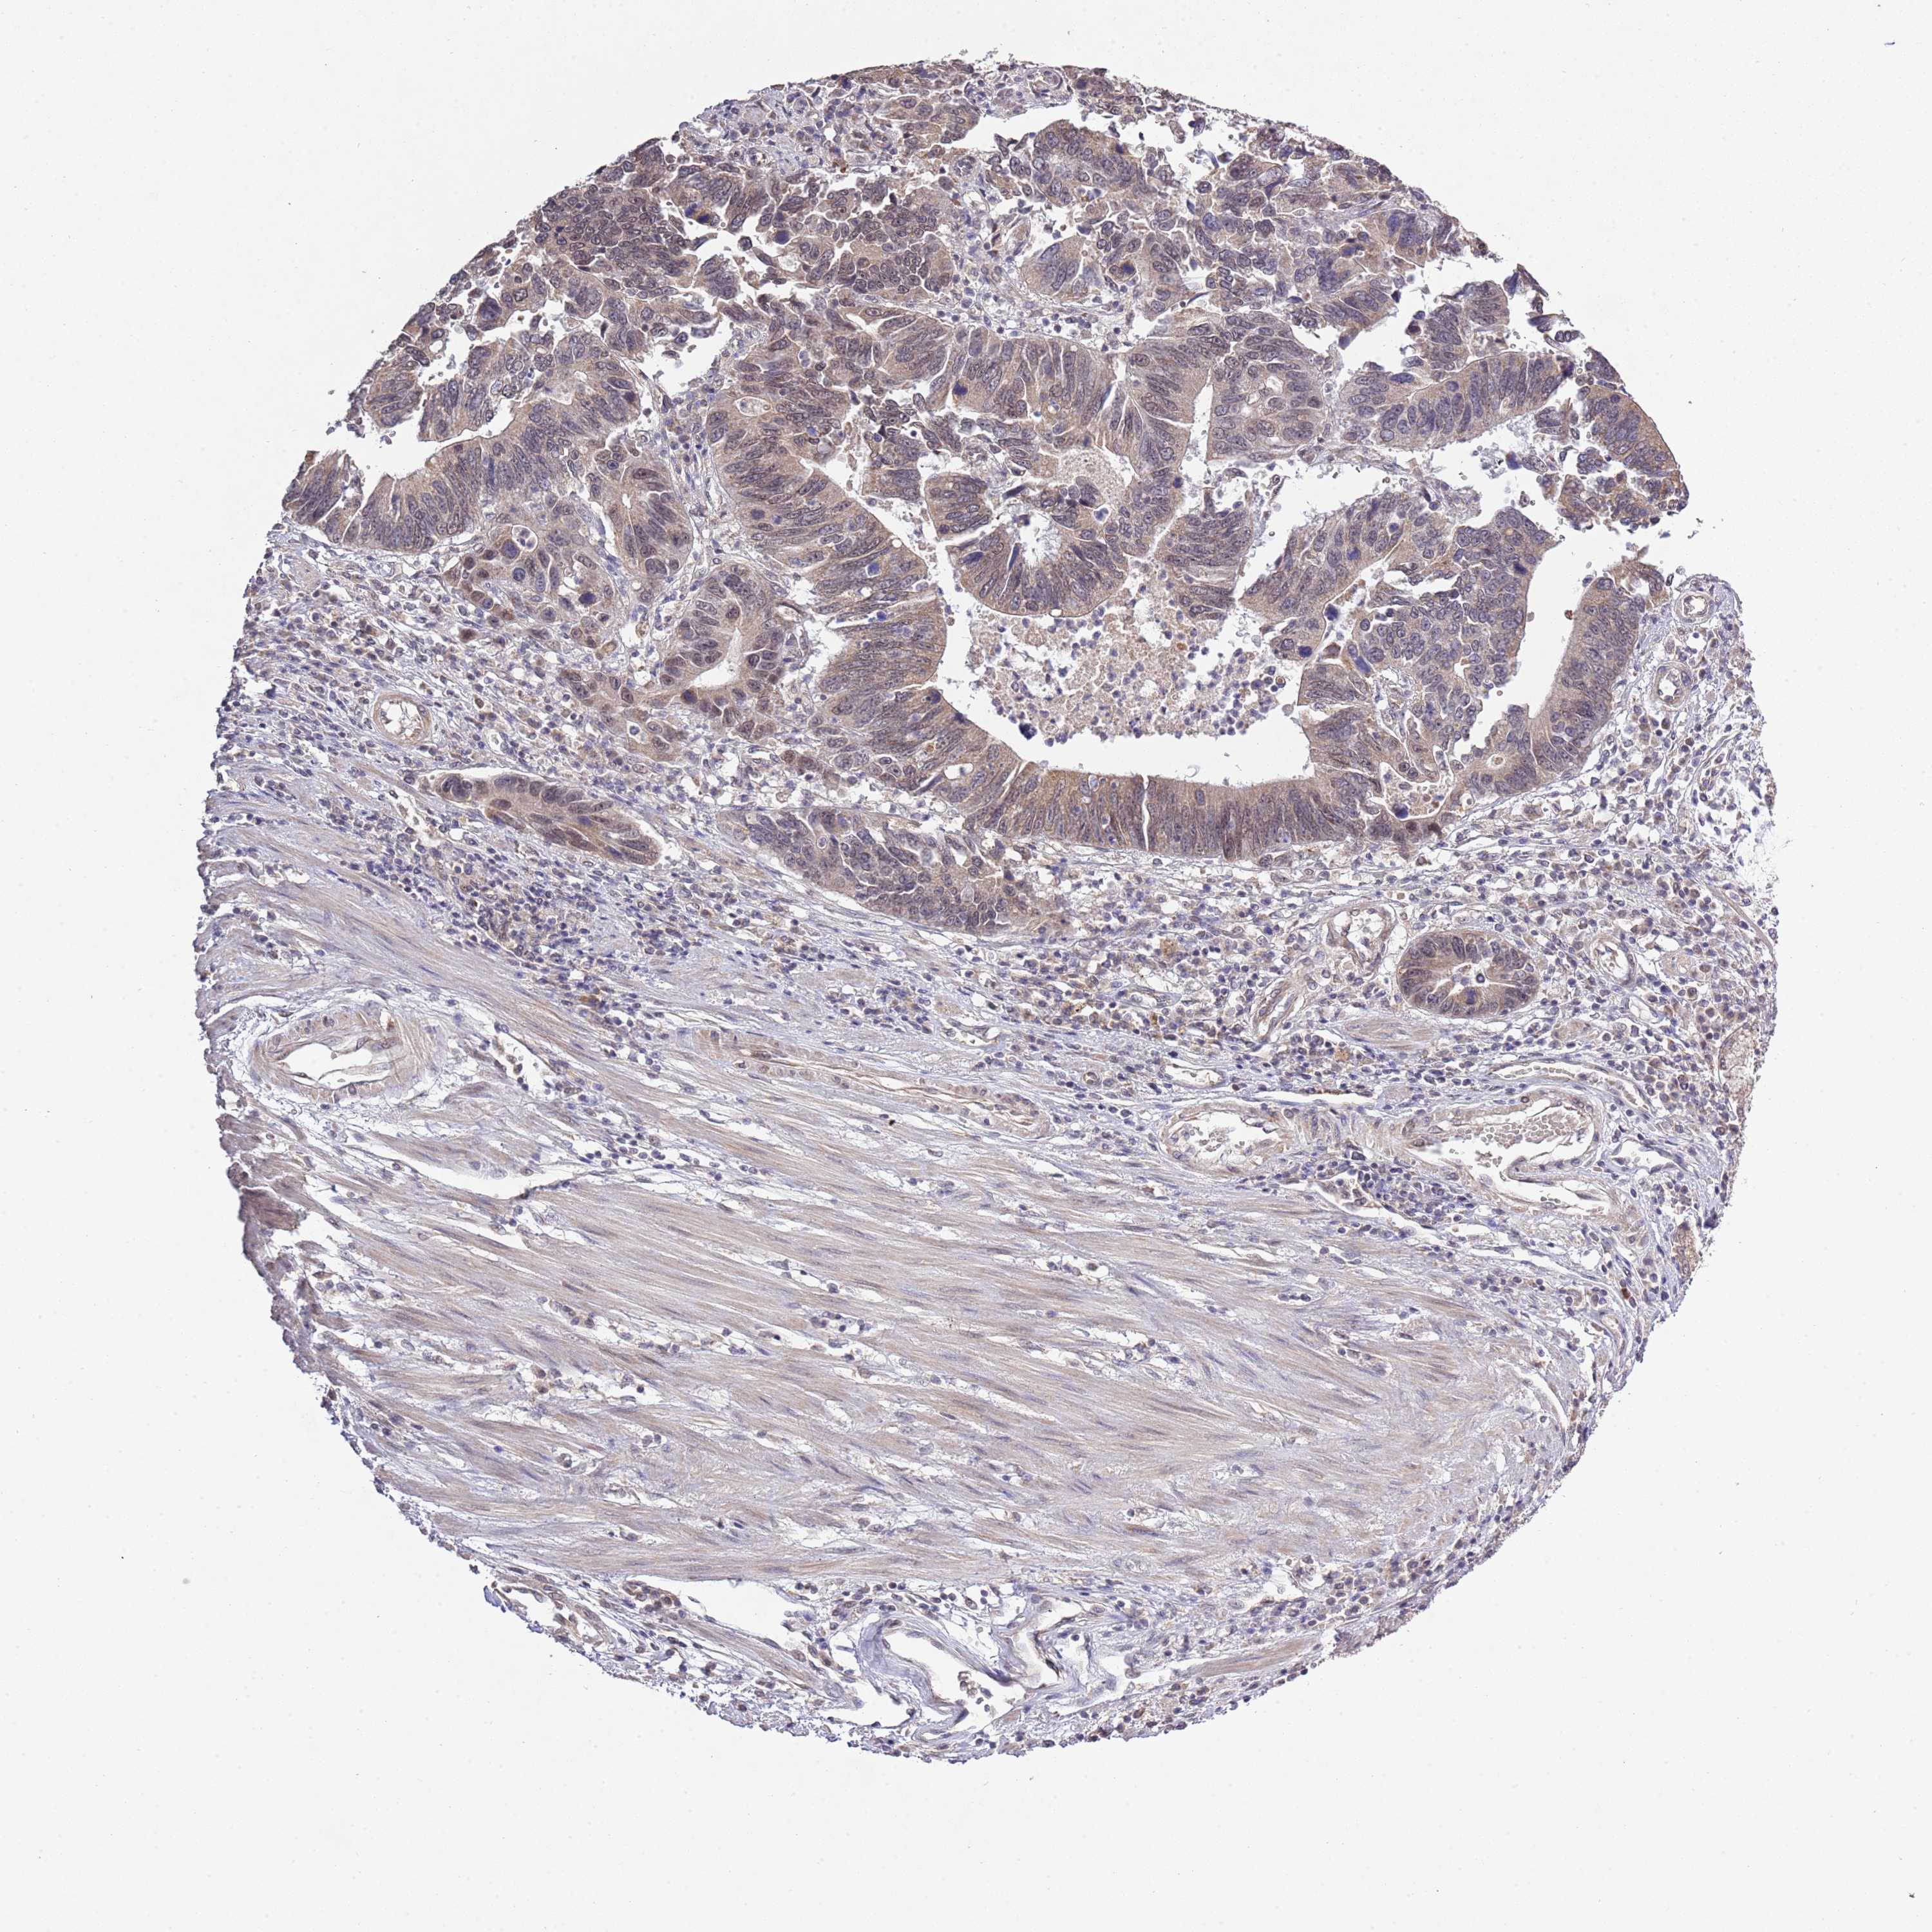

STOMACH CANCER - Protein expressioni

A mouse-over function shows sample information and annotation data. Click on an image to view it in a full screen mode. Samples can be filtered based on level of antibody staining by selecting one or several of the following categories: high, medium, low and not detected. The assay and annotation is described here.

Note that samples used for immunohistochemistry by the Human Protein Atlas do not correspond to samples in the TCGA dataset.

Antibody stainingi

Antibody staining in the annotated cell types in the current human tissue is reported as not detected, low, medium, or high, based on conventional immunohistochemistry profiling in selected tissues. This score is based on the combination of the staining intensity and fraction of stained cells.

Each image is clickable and will lead to virtual microscopy that enables deeper exploration of all samples and also displays staining intensity scores, fraction scores and subcellular localization as well as patient and tissue information for each sample.

Antibody HPA041391

Antibody HPA044250

Staining

High

Medium

Low

Not detected

Intensity

Strong

Moderate

Weak

Negative

Quantity

>75%

75%-25%

<25%

None

Location

Nuclear

Cytoplasmic/membranous

Cytoplasmic/membranous,nuclear

Adenocarcinoma, NOS

Adenocarcinoma, High grade